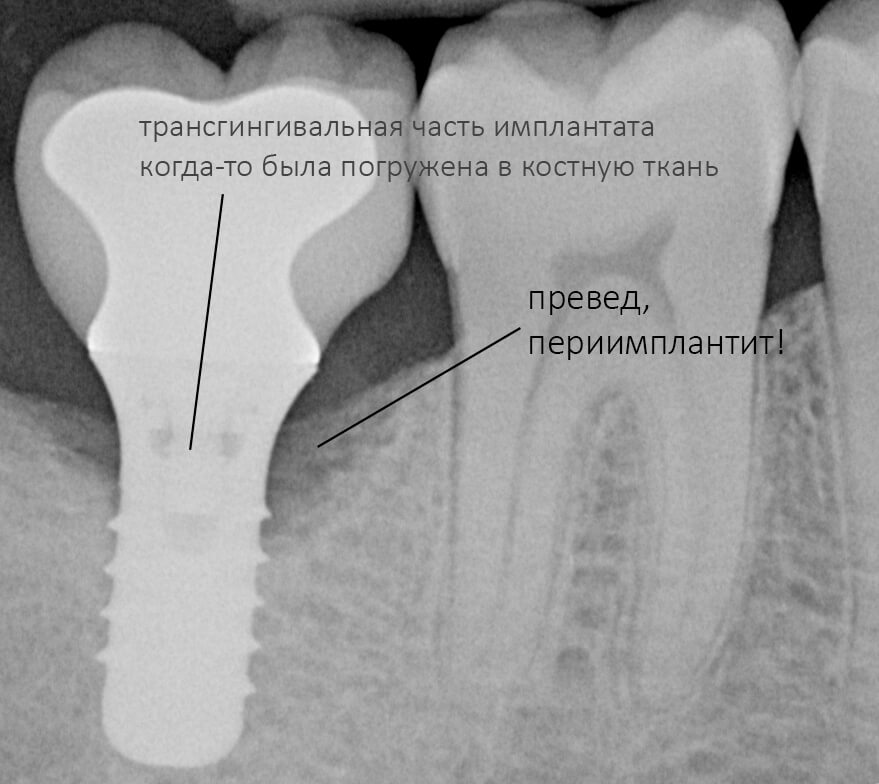

Следовательно, имплантат погружается на такую глубину, чтобы его полированная часть всегда оставалась выше уровня костной ткани. Не рекомендуется, не нужно, да и просто нельзя погружать трангингивальный имплантат в костную ткань до уровня ортопедической платформы! Это, кстати, одна из самых распространенных ошибок на имплантах Zimmer Spline и Straumann Standart (TL). Почему? потому, что хирургический протокол не предполагает подготовку лунки под расширяющуюся трансгингивальную часть, в результате она создает избыточное давление на окружающую кортикальную кость, а это, как говорится, превед, периимплантит. И примеров тому масса.

Вновь обращаясь к тезису о полированных частях имплантата, повторюсь, что они должны находиться выше уровня костной ткани. Почему? Всё по тем же причинам, что и с трансгингивальными имплантами: хирургический протокол не предполагает субкрестального погружения субгингивальных имплантатов даже при условии подготовки лунки большей глубины. Например, вот протокол установки Nobel Replace CC 4.3×13:

Это картинка с официальной презентации Nobel Biocare. Ни в ней, ни где-либо еще нет упоминания о возможности субкрестальной установки Nobel Replace CC. Так откуда пошла мода «топить» эти имплантаты глубоко в костную ткань?

Кроме того, я должен напомнить, что к полированным частям имплантата, тем более к абатменту костная ткань не прирастает — а это значит, что мы заранее создаем трудноочищаемый костный карман между абатментом и стенкой лунки — и снова превед, периимплантит! И, наконец, третья причина — отсутствие супраструктур нужной трансгингивальной глубины, что может создать сложности при протезировании. Поэтому вполне может оказаться, что субгингивальный имплантат, установленный субкрестально, будет невозможно протезировать цивилизованными методами, как, например, на этом снимке:

Это, кстати, работа известного московского специалиста в области имплантологии)).